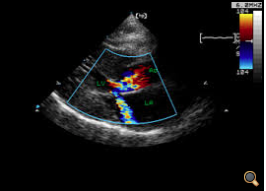

Im Ultraschallbild rechts sieht man stark verdickte Herzwände. Man kann ein Herzgeräusch im Doppler erkennen. Es besteht die akute Gefahr einer Thrombembolie. Leider ist es kaum möglich die HCM im Vorfeld durch Röntgen festzustellen. HCM findet man hauptsächlich bei Maine Coon und Ragdollkatzen. Die Krankheit wird durch autosomal rezessive Gene vererbt.